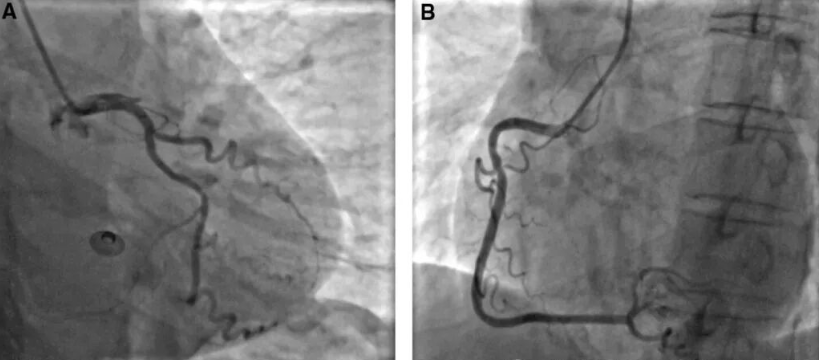

据报道,在二次谐波、高频探头和造影剂辅助下, 前降支(LAD)远段成像成功率高达100%,后降支(PDA)则为33-97%。尽管这项技术需要经验和实践,并且只有熟练的操作人员才能在冠状动脉可视化方面达到90%的成功率,但在临床中是值得探索和实践的。

LAD和PDA远端,靠近胸壁,故超声成像成功率,远远高于位置较深的LAD近端、Cx和RCA,后者可考虑使用标准低频探头,以提高声束穿透力。二次谐波技术的出现,心底处组织的图像质量提升,极大地促进了整个冠状动脉树的检查。